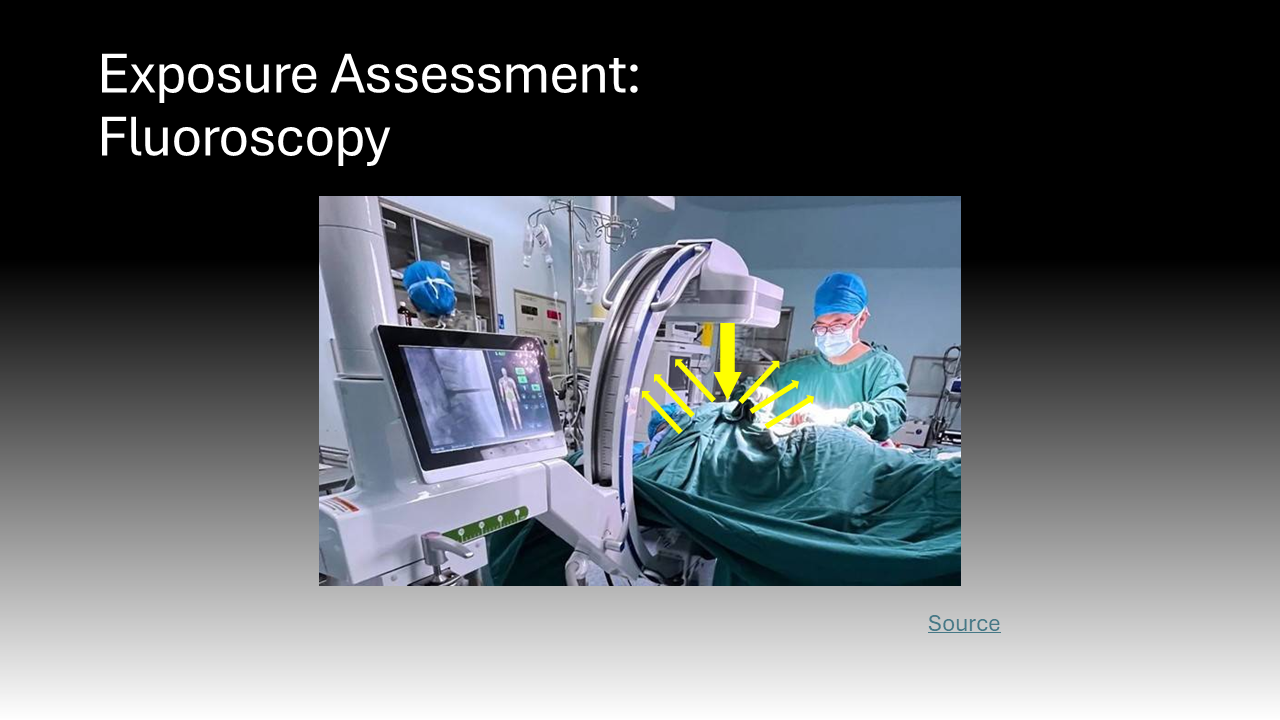

Ionizing radiation encompasses all high-energy rays that detach electrons from atoms. The body absorbs a fraction of this energy, which is disruptive at the molecular level.2 Ionizing radiation is found at low levels in the natural environment but has been employed at higher doses in medicine since the late 19th century.3 X-rays are ubiquitous in healthcare; this ionizing radiation has been the basis of two-dimensional diagnostic images and CT scans for years but is now employed during procedures.3 Cardiologists, neurosurgeons, orthopedic and vascular surgeons, and interventional radiologists all use live, continuous fluoroscopic imaging intraoperatively for “real-time feedback” during procedures.4 This technology not only allows for more accurate interventions but enables the use of minimally invasive approaches that replace open surgeries.4 In sum, the expanding use of X-ray technology in medicine, especially over the past 20 years, has led to more efficient diagnosis and treatment that is safer and more tolerable for patients.5 However, it also exposes a more diverse number of physicians to radiation and its harmful effects.5 Whereas X-rays during a diagnostic image or cancer radiation treatment are delivered to a physically isolated patient, physicians must be in close proximity to patients and radiation sources to perform procedures.5 This creates the current dilemma where healthcare providers now comprise the largest group of workers exposed to radiation in the world.5

The effects of radiation are dose-dependent.6 This means that while the potential damage from the low doses of radiation used during a medical procedure is slight, it is the cumulative effects of this chronic exposure in healthcare workers that are worrisome.6 It is logistically challenging to track radiation exposure in the healthcare setting because there are different types of dosimeters and various sets of guidelines for their use that differ by institution.7 Additionally, though they are mandated to wear dosimeters, individuals vary in their compliance with safety practices and protective shield use, which will be discussed later.7 While data on US physicians is lacking, several retrospective cohort studies in Europe have determined levels and trends of radiation exposure in healthcare workers.7 The standard unit for radiation is a gray (1 joule of energy absorbed by 1 kilogram) but when considering the harmful effects of radiation, grays are multiplied by a quality factor to convert to Sieverts (Sv).4

Behavioral modifications and personal protective equipment also play a key role in risk mitigation for those exposed to intraoperative radiation.4 When surgeons stand further away from the radiation source, they are exposed to an inversely proportionally decreased dose of radiation.4 Additionally, simply standing on the same side as the receiver significantly reduces the exposure to the scattering radiation as it bounces off the receiver.4 Following the establishment of the Advisory Committees on X-Ray and Radium Protection in the late 1920s, recommendations and regulations requiring the availability and use of lead protection devices and shielding devices have significantly curbed the negative effects of intraoperative scatter radiation exposure.16 These policies were adopted by the Occupational Health and Safety Administration (OSHA) and local hospitals, such as Stony Brook University Hospital.17–20 Lead aprons can reduce exposure by up to 90%, lead collars can reduce thyroid exposure 9-fold, lead gloves can reduce hand exposure by 75%, lead glasses can reduce exposure by up to 70%, and shields can offer significant reductions.4,21